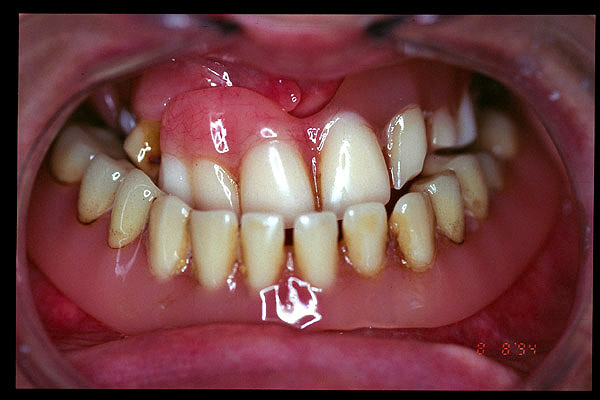

CM Enfermedad periodontal avanzada